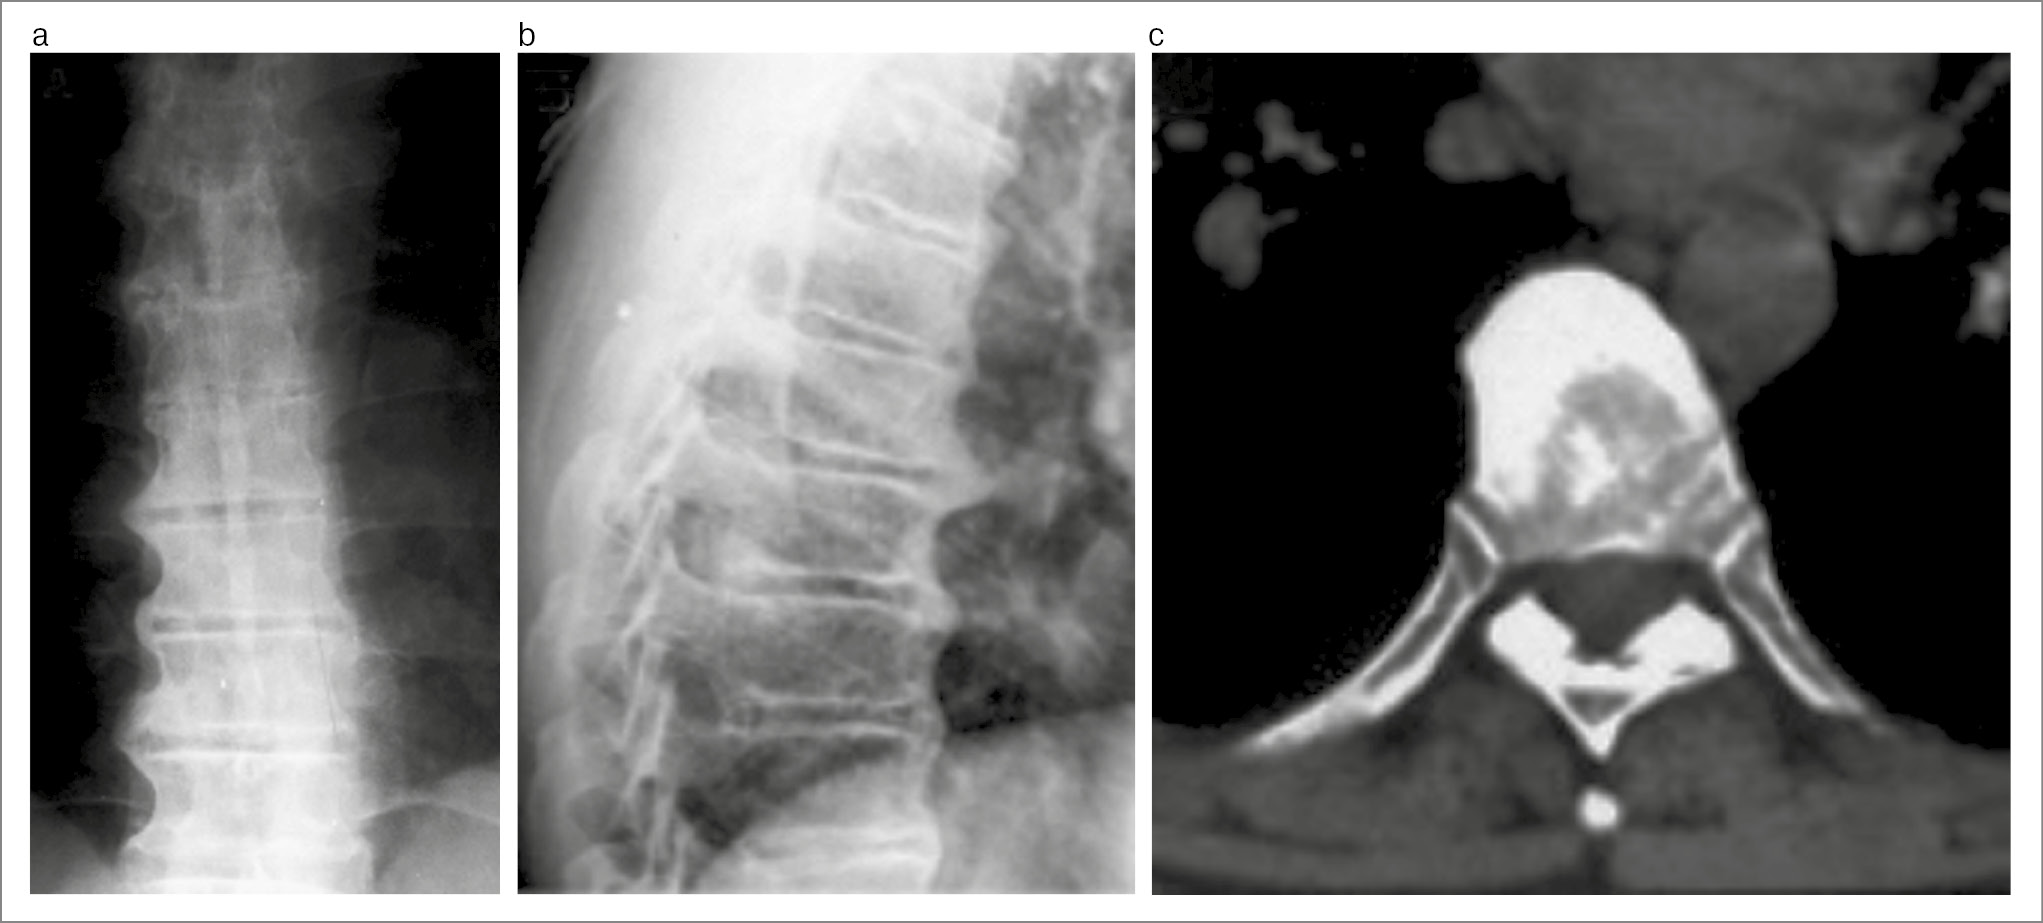

Перед детальным анализом обзорного рентгеновского снимка костей таза рекомендуется определить качество изображения КПС, и, если оно нечеткое, целесообразно проведение КТ [17]. Использование этого метода рекомендуется и в том случае, если при просмотре обычного снимка возникает подозрение на сакроилиит. Преимущества КТ для выявления структурных изменений КПС (не только по сравнению с плоскостной рентгенографией, но и с МРТ) иллюстрируются рис. 6 и 7 (исследования проведены с небольшим интервалом). Рентгенография КПС в косых проекциях, а также сцинтиграфия скелета для диагностики сакроилиита имеют лишь историческое значение.

Рис. 6. Пациент М. 25 лет. Диагноз АС, HLA-B27+, длительность болей в нижней части спины 3 года: a – на рентгенограмме видны только участки субхондрального склероза подвздошных костей с обеих сторон (I стадия сакроилиита); b – КТ (коронарная проекция) показала широкие зоны субхондрального склероза с двух сторон, немногочисленные эрозии (II стадия сакроилиита); c – МРТ (коронарная проекция, режим Т2 STIR): участки отека костного мозга (светлые области в субхондральных отделах подвздошной кости и крестца справа), эрозия подвздошной кости в зоне отека (активный сакроилиит по классификации ASAS).

Рис. 7. Пациент П. 24 лет. Диагноз АС, HLA-B27+, длительность болей в нижней части спины 1 год: a – рентгенограмма: широкая зона субхондрального склероза в левой подвздошной кости (I стадия сакроилиита); b – КТ (коронарная проекция): множественные эрозии подвздошных костей с псевдорасширением щели обоих суставов, широкий субхондральный склероз подвздошных костей (III стадия сакроилиита); c – МРТ (коронарная проекция, режим Т2 STIR): многочисленные зоны околосуставного отека костного мозга (светлые области) и эрозии в подвздошных костях и крестце с обеих сторон (активный сакроилиит по классификации ASAS).

На рис. 7 видно, что с помощью КТ обнаруживается больше характерных для сакроилиита структурных изменений (эрозии, склероз, псевдорасширение щели), чем на МРТ. Еще одним преимуществом КТ у пациентов с предполагаемым АС/аксСпА является более объективная верификация тех изменений, которые могут имитировать сакроилиит на МРТ: аномалии развития, незавершенные зоны роста, конденсирующий остеит, остеоартроз и болезнь Форестье (идиопатический диффузный гиперостоз скелета). Для оценки КПС и позвоночника используются мультисрезовые (мультиспиральные) компьютерные томографы. Число срезов не должны быть меньше 16. Существенно соблюдение следующей методики исследования. Верхняя граница сканирования располагается на уровне верхнего края крыльев подвздошных костей, нижняя – на уровне нижнего края тел лобковых костей. Сканирование проводится без наклона устройства гентри. Рекомендуемые технические параметры: толщина среза – 1 мм, шаг спирали – 3 мм, параметр питч – 0,94, время сканирования – 12 с, напряжение на трубке – 140 kVp, сила тока на трубке – 300 mAs. Для диагностики сакроилиита может и должна использоваться (особенно у лиц молодого возраста) низкодозовая КТ [18]. Осуществление протокола низкодозового исследования возможно на любом современном КТ-сканере, для чего изменяют параметры сканирования в настройках аппарата. Доза облучения при этом снижается примерно в 10 раз и сравнима с лучевой нагрузкой во время выполнения обзорного снимка костей таза.